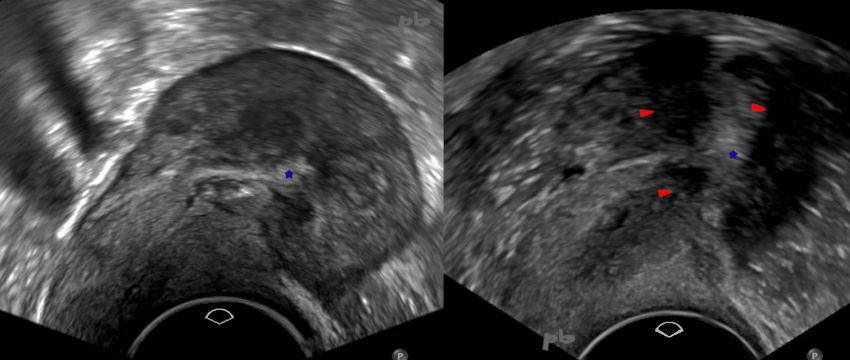

Echographie endovaginale – Coupe transversale sur l’utérus.

Endomètre bien visualisé (★), avec une striction (flèches) au milieu par disparition du revêtement muqueux de la cavité.

Images en rapport avec les antécédents de tuberculose utérine et de chirurgie.